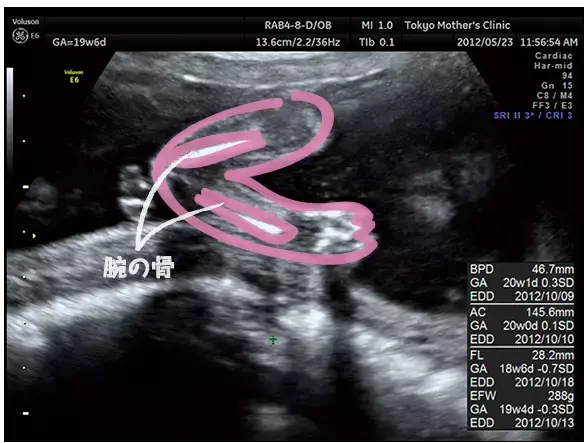

妊娠19週のエコー写真

大きく成長してパーツごとの写真に

身長が大きくなり、モニターに全身像が入りきらなくなってくるため、だんだんエコー写真も頭だけ、下半身だけ、とパーツごとになってきます。指の動きが複雑にできるようになり、ますます動きが人間らしくなるでしょう。また、胎盤の位置や子宮口の様子など、母体に異常はないかも確認しています。

腕を曲げた様子、指の様子もはっきり分かるエコー写真。骨は白く写るので分かりやすい。